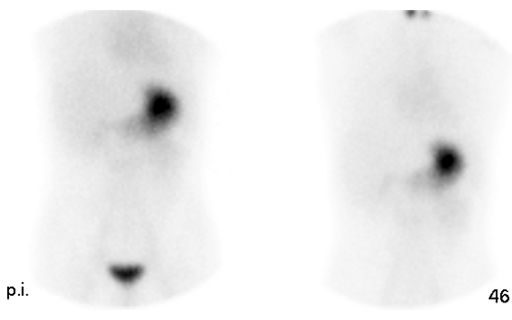

Una gammagrafía ósea implica inyectar una cantidad muy pequeña de material radiactivo (marcador) dentro de una vena. La sustancia viaja a través de la sangre hasta los huesos y órganos. A medida que esta va desapareciendo, emite un poco de radiación. Esta es detectada por una cámara que lentamente escanea el cuerpo.

Toma imágenes del marcador que hay en sus huesos. El técnico puede solicitarle que cambie de posición durante el procedimiento. Esto ayuda a obtener imágenes desde diferentes ángulos. Una gammagrafía ósea de todo el cuerpo tarda aproximadamente 1 hora en completarse.